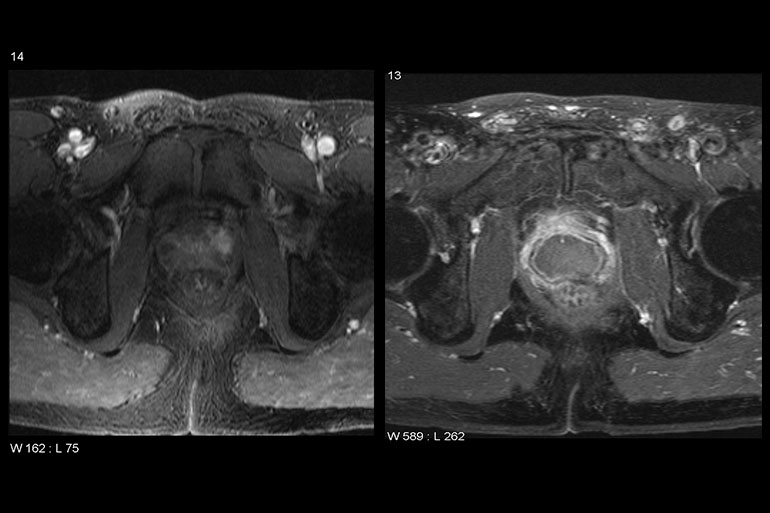

Prostate MRIs are displayed on the SonaCare website. (Courtesy of SonaCare)